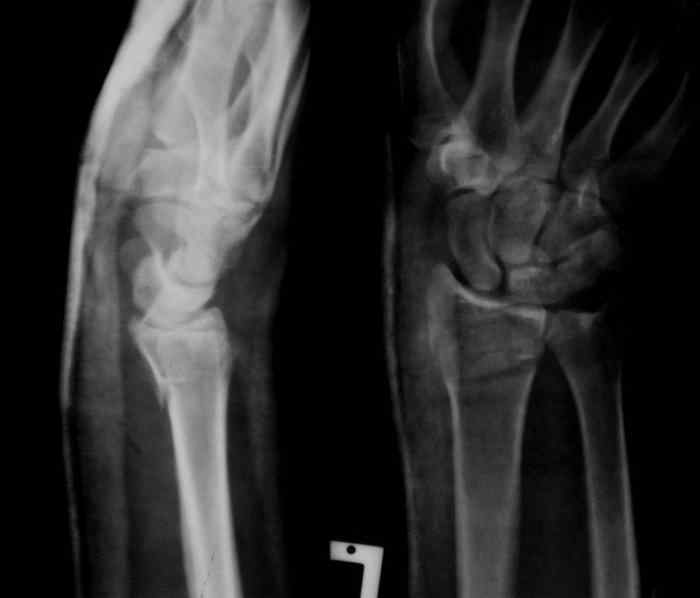

Под проводниковой анестезией произвел аккуратную одномоментную репозицию, фиксацию гипсовой повязкой в положении умеренной экстензии. Думаю неплохо получилось. Мягкие ткани не вызывали опасений в плане Зудека.

Спасибо.

13.12.2007.jpg

37KB (38539 bytes)